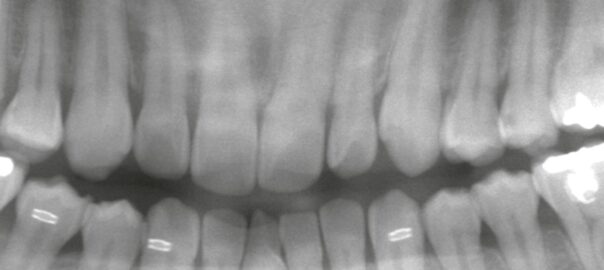

【上顎埋伏親知らず】見えない位置にある歯をどう抜くか ― CTが変えるアプローチ

【症例】排膿を繰り返す埋伏親知らず|嚢胞を伴うケースの抜歯